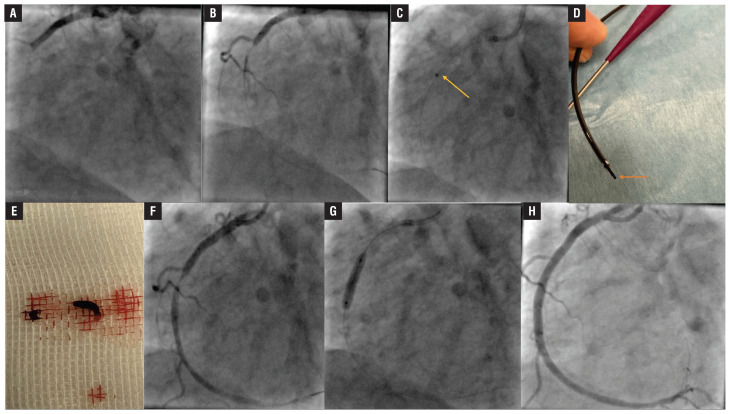

Continuous mechanical aspiration thrombectomy for STEMI with high thrombus burden.